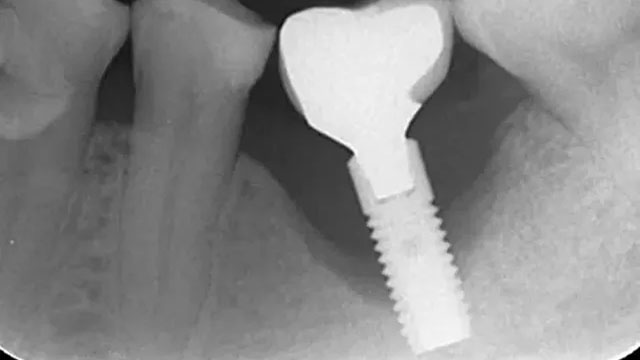

他院にてインプラントを抜かないと治らないと言われたインプラント周囲炎のケースです。

インプラント周囲炎の患者様の症例です。

歯ぐきが腫れて、排膿がある左上6番にブルーラジカル治療を行い、歯周ポケットが5mm改善しました。

インプラント周囲の歯周ポケットを触ると排膿があったため上部構造を外しブラッシング指導を行いました。

ブラッシング指導である程度の改善はみられたものの完全に改善したとは言えない状態でした。

施術前は歯周ポケットは深いところで9mmありましたが、施術後は4mmになって、歯肉がしっかり引き締まりました。

排膿もなくなりました。